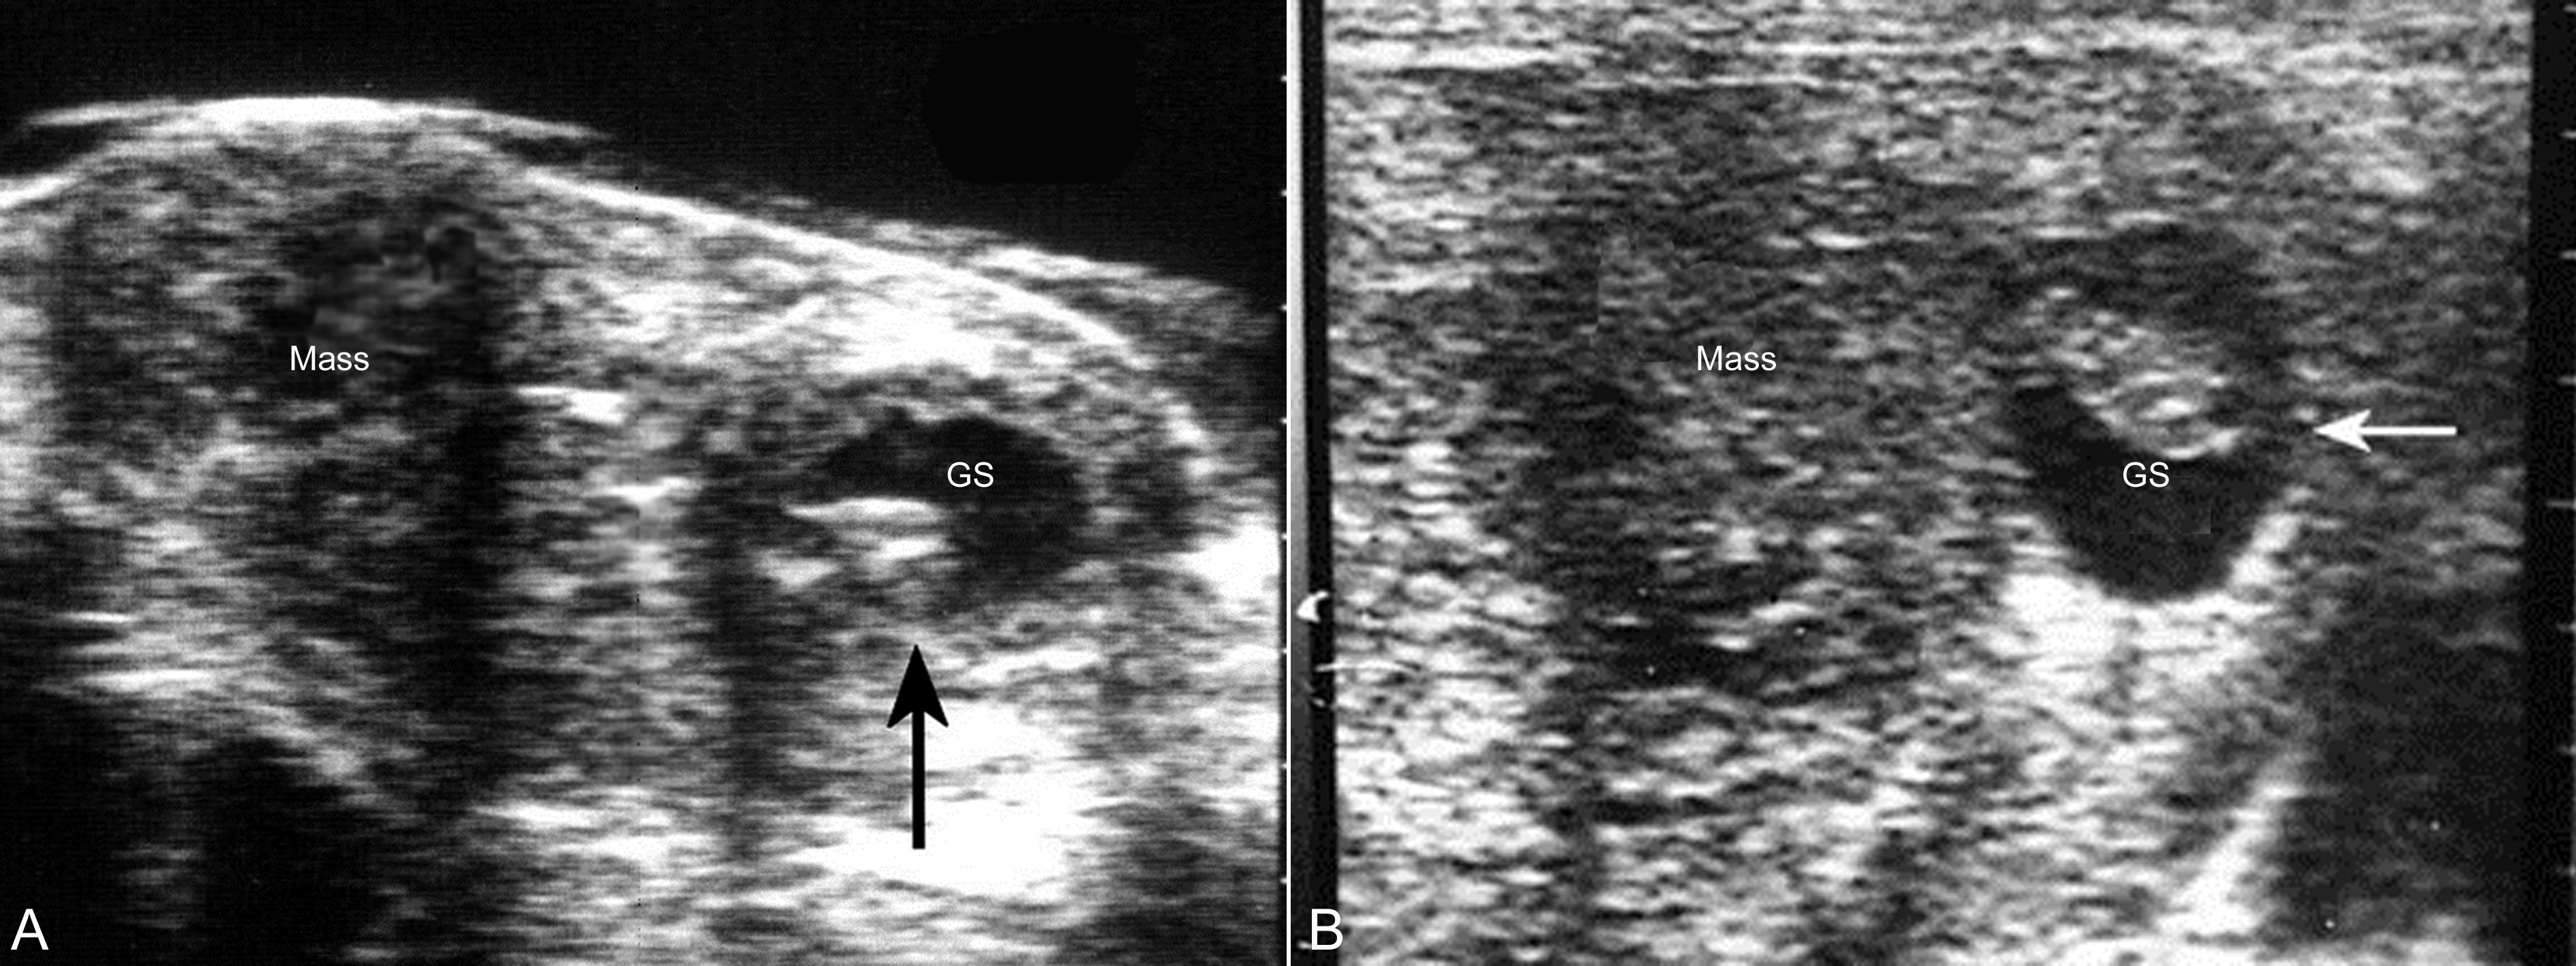

图2妊娠合并子宫肌瘤声像图

子宫体部右侧壁可见肌瘤(Mass)回声,孕囊(GS)向左侧移位,箭头示孕囊内的胚胎回声